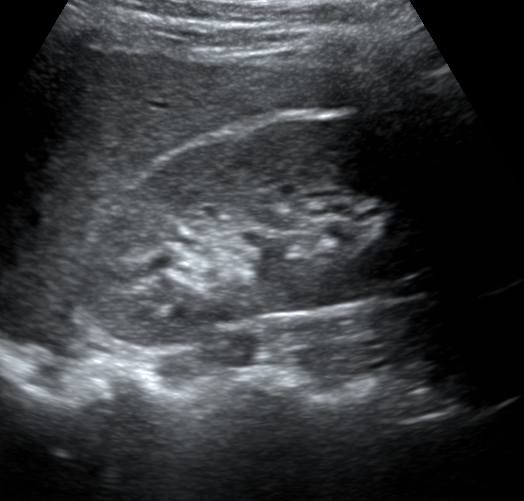

Gallbladder

The gallbladder is visualized in this scan at the center of the image. In addition, the portal vein is the circular struction with a hyperechoic wall left of the gallbladder in this scan. The inferior vena cava is the cylindrical structure right of the liver.